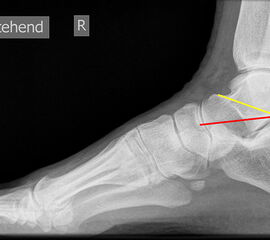

TMT-1-Gelenk lateral (Tarsometatarsale-1-Gelenk)

In der Seitaufnahme wird eine plantare Öffnung des TMT-1-Gelenks als Indikator für eine Instabilität gewertet. Coughlin et al. 5 definierten einen Winkel zwischen der proximalen Gelenkfläche des Os metatarsale I (gelb) und der distalen Gelenkfläche des Os cuneiforme I (rot). (Norm: ±0° 5).